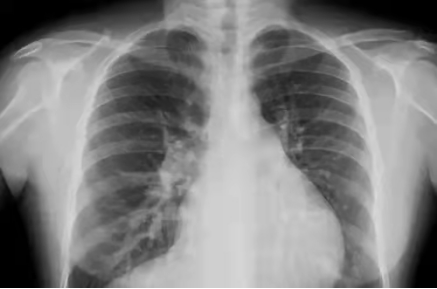

影像舉例

胸片能夠顯現(xiàn)我們的肺、心臟、縱膈、氣管,這么多器官都在一張片子上,所有器官的影像前后壓縮,變成了一張平片。所以,X線片是很多器官重疊在一起。

但是,如果肺部顯示有陰影,是肺結(jié)核?肺炎?還是腫瘤?X線是不能辨別的。